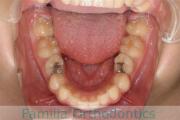

歯並びを治したいということで小学生のときに来院されました。二期治療で小臼歯抜歯の可能性が高いと判断しましたが、スペースの不足が著しいため、上下を拡大してから成長観察に移行しました。

左下犬歯に異常があったので、この歯と左右上&右下の小臼歯を抜歯してマルチブラケットを行いました。約4年、30回以上の通院が必要でした。

- ≫治療中 ステップ1

- ≫治療後

左下犬歯の形成異常は原因がわかりませんでした。犬歯は寿命の長い大事な歯なので、抜くことにはリスクがありますが、本ケースではやむを得ない判断だったと思います。